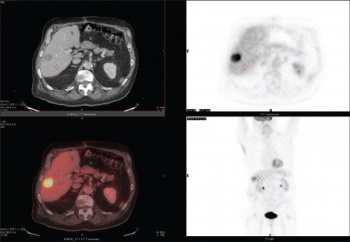

PET is typically combined with CT (PET-CT) to provide detail on the metabolic activity of tumours and to detect metastatic disease (see Figure 4). In Ireland, a number of cancers, depending on the stage of the initial cancer on cross-sectional imaging and on the type of malignancy, will have additional staging with PET-CT. The Faculty of Radiologists provides guidelines based on international standards outlining current indications for PET-CT.6 If histological confirmation is required an ultrasound or CT-guided biopsy is often performed by the radiologist.

Figure 4. PET-CT demonstrating avid tracer uptake in a solitary hepatic lesion consistent with a malignancy

Figure 4. PET-CT demonstrating avid tracer uptake in a solitary hepatic lesion consistent with a malignancy(click to enlarge)